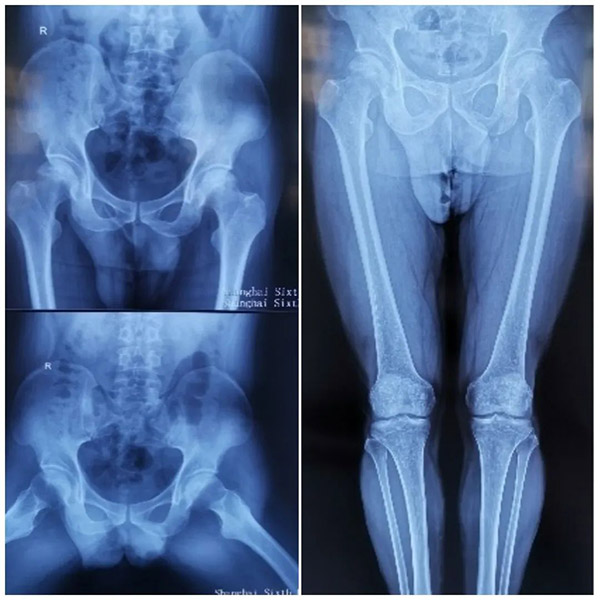

在黑龙江当地的医院,赵大哥接受了双侧髋关节MRI检查,发现双侧股骨头不规整,其内信号不均。压脂呈高信号,以左侧为主。检查意见为双侧股骨头缺血性坏死。

入 院后,经过进一步检查,赵大哥左侧腹股沟中点压痛阳性,左髋部外侧压痛阳性,轴向叩击痛阴性,左髋关节活动明显受限,“4”字征阳性,麦氏征阳性;右侧腹 股沟中段深压痛阳性,行走不受影响,但无法蹲踞或剧烈活动。双下肢皮肤感觉正常,两脚各足趾活动自如,足背动脉搏动有力,末梢血运正常。